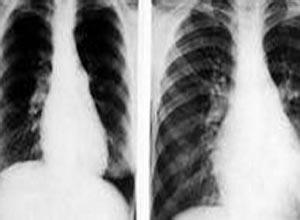

简介过敏性肺炎(hypersensitivity pneumonitis)是一组由不同致敏原引起的非哮喘性变应性肺疾患,以弥漫性间质炎症为其病理特征。系由于吸入各种有机物尘埃,含有真菌孢子,细菌产物、动物蛋白质或昆虫抗原的有机物尘埃微粒(直径<10μm)所引起的超敏感性反应引起。因此又称为外源性变应性肺泡炎(extrinsic allergic alveolitis),1932年有人首先提出农民肺,是由于暴露于发霉的干草所致。最近更广泛地用免疫学技术,观察不同抗原和不同暴露情况的各种类似疾病。